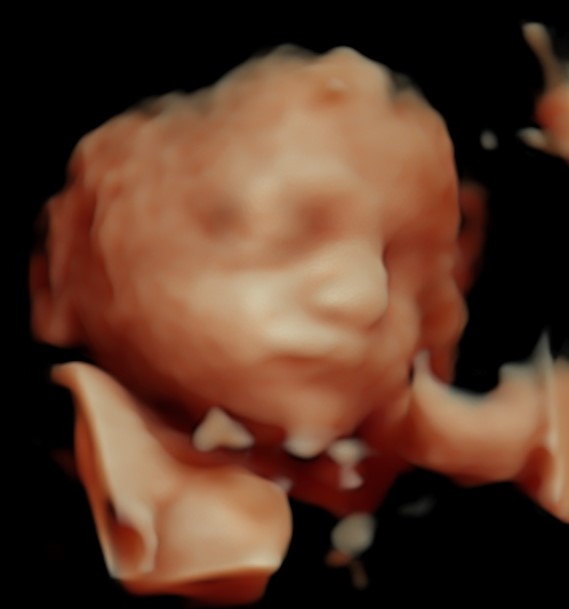

Monmouth County’s First 4D/5D/HD Live Ultrasound Studio

4D/5D/HD Ultrasound Gallery

Gallery